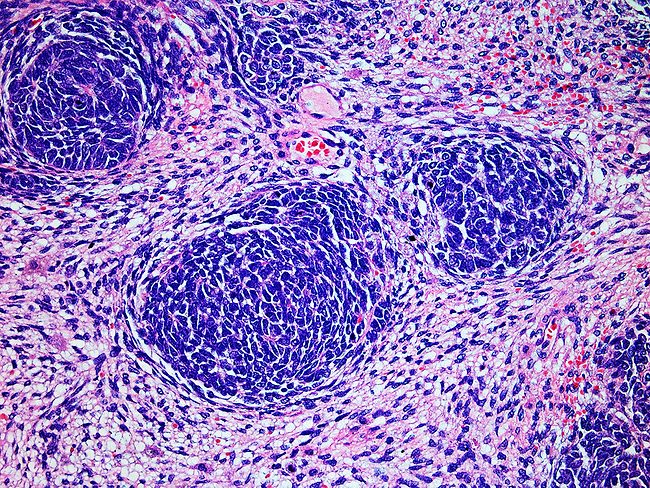

Illustration of knee joint, giant cell tumor of bone

Synox en route to approval on positive phase III for TGCT

Synox Therapeutics Ltd. is preparing to file for FDA approval of emactuzumab in treating tenosynovial giant cell tumor (TGCT), after announcing positive top-line phase III results.